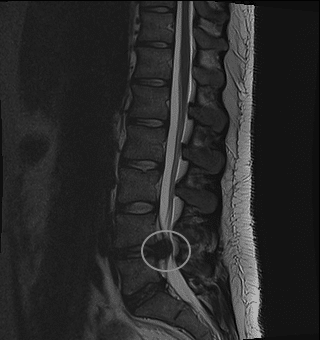

While X rays and CT scans are very good at visualising high density tissue, magnetic resonance imaging or MRI is better at visualising soft tissues. Therefore, it is very good at being able to detect certain soft tissue masses and tumours. Images with an MRI can be presented in the sagittal, coronal or transverse plane.

Depending on the weighting of the image different soft tissue structures appear bright and dark on an MRI. T1 weighted images are ones where the fat appears bright, but fluid appears dark. T2 images on the other hand represent fluid as bright and fat as dark.